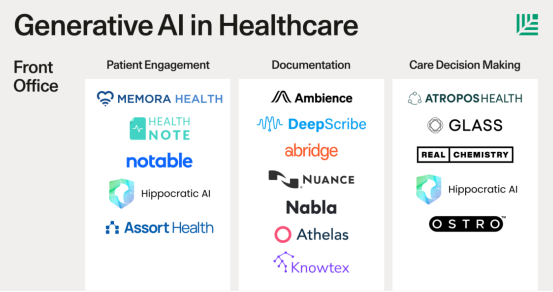

在《Generative AI in Healthcare》这篇报告中,红杉提到了目前AI在医疗领域的一些重要应用,这其中就包括了如患者互动、文档记录、临床决策等。

在红杉资本看来,现在的医疗AI,已经跃过了“锦上添花”的阶段,开始对医疗行业的核心环节进行赋能,而这样的赋能,则大大提高了医疗领域的效率和质量,降低成本和人力。

具体来说,医疗行业的核心环节,包括了患者互动、文档记录、临床决策、预授权、编码和收入周期管理等六大环节。